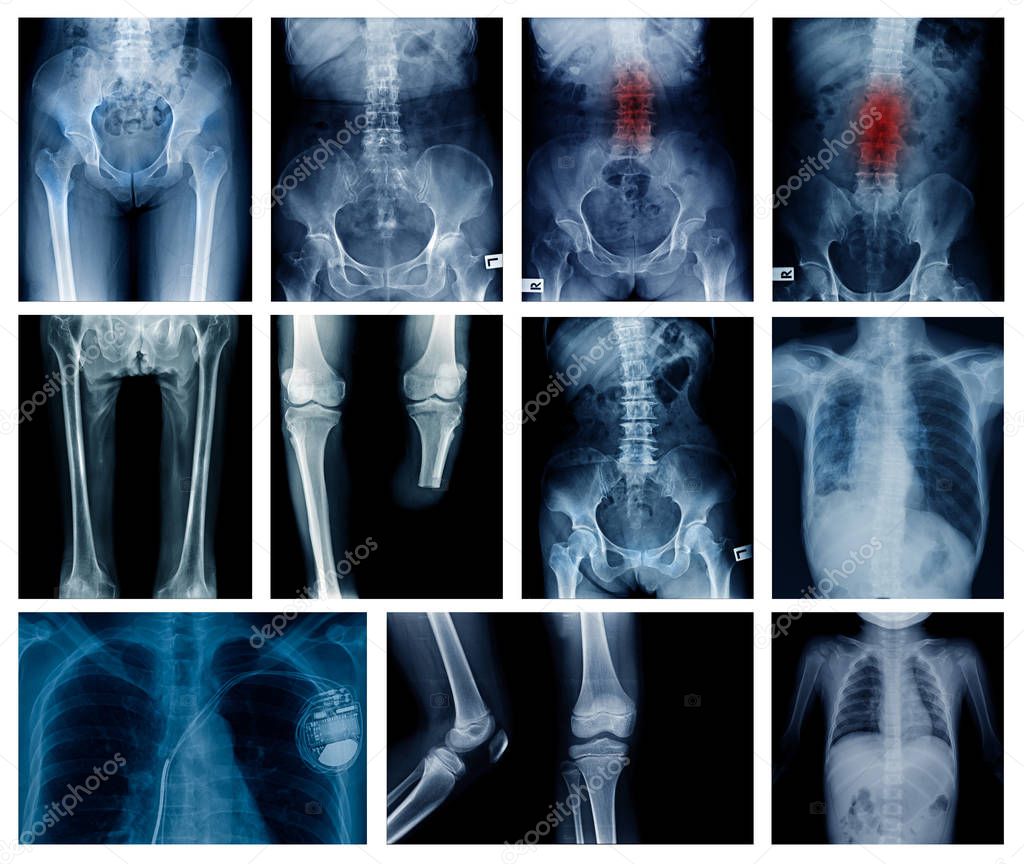

Colección De Alta Calidad De Imagen De Rayos X Muestran Muchas Partes

www.deperu.com

www.deperu.com

Rayos X De Cuerpo Completo Fotografías E Imágenes De Alta Resolución

www.alamy.es

www.alamy.es

Rayos X Cuerpo Humano 2024

www.deperu.com

www.deperu.com